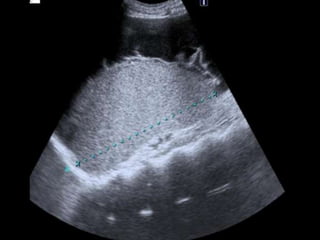

La rotura espontánea del bazo es una causa rara pero potencialmente letal de dolor abdominal que puede deberse a alteraciones congénitas, infecciones, enfermedades metabólicas, neoplasias, inflamación o alteraciones vasculares. Los síntomas incluyen dolor abdominal que se generaliza, distensión abdominal y signos de irritación peritoneal. El diagnóstico se realiza mediante cuadro clínico, exámenes de laboratorio, placa de abdomen, ecografía, lavado peritoneal o TC, y el tratamiento implica líquidos intra